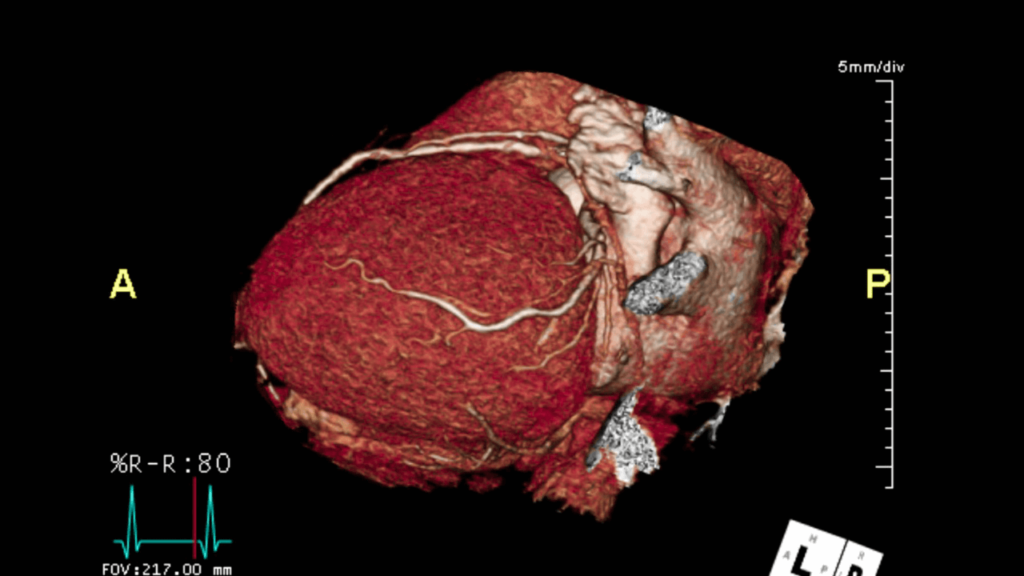

By combining high-resolution CT technology with an intravenous contrast agent, CTCA produces detailed 3D images of the heart vessels, allowing precise evaluation of blockages, vessel narrowing, plaque burden, and calcium deposits-often before symptoms become severe.

During the procedure, contrast dye is administered through a peripheral vein, while a high-speed CT scanner captures images synchronized with the cardiac cycle.

This advanced timing significantly reduces motion artifacts and ensures clear visualization of even small coronary branches.

Cardiac CT imaging allows clinicians to assess vessel anatomy, plaque characteristics, and overall cardiac structure in a single examination.